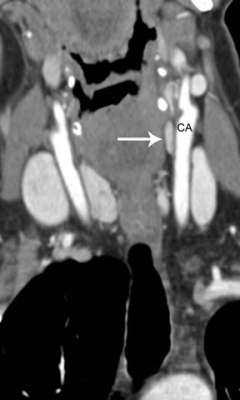

Coronal 4D-CT image of a parathyroid adenoma

Coronal 4D-CT image of a parathyroid adenoma within the left carotid sheath. CA, carotid artery.